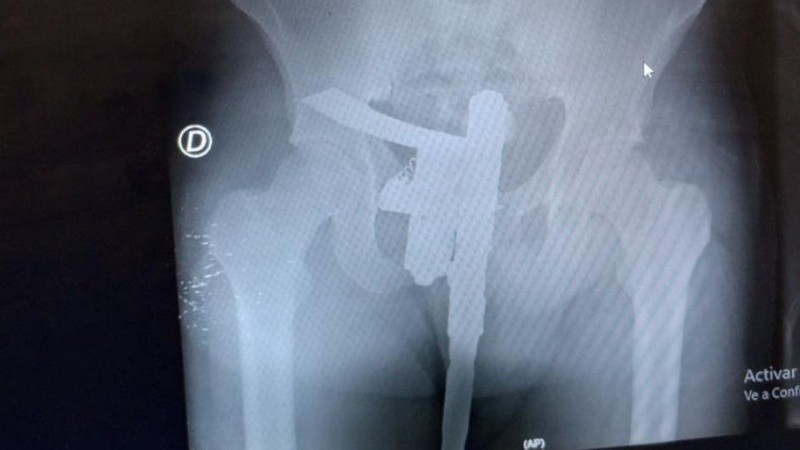

Pero al momento de revelar la radiografía, el enfermero vio que el hombre tenía una pistola de fabricación casera escondida a la altura de los genitales. Ante esto dio aviso al Comando Radioeléctrico que acudió al lugar, requisó al paciente, le secuestró el arma y se lo llevaron detenido a la seccional 4ª.